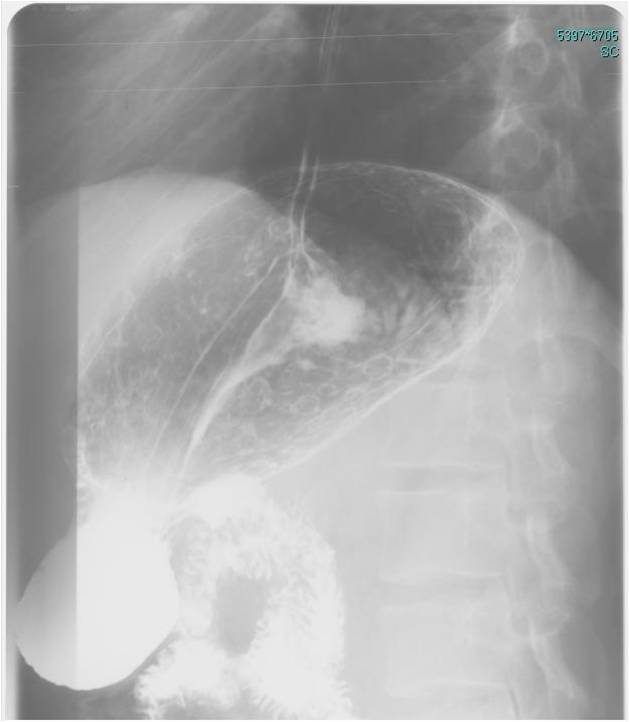

Image Image

Fig.8., 9.:Incarcerated hiatus hernia

A middle aged female with eight day history of abdominal pain was emergently admitted to the surgery department. The chest and abdominal radiographs showed no alteration, thus the patient was released home. Four days later she was readmitted to a different hospital where the upper GI series revealed an incarcerated hiatus hernia. Surgical exploration confirmed perforation of the ulcerated wall in the incarcerated gastric segment. Second review of the initial chest x-ray a found a right lower mediastinal soft tissue mass that had already been present at the time.

Upper GI series must be always performed in these patients!